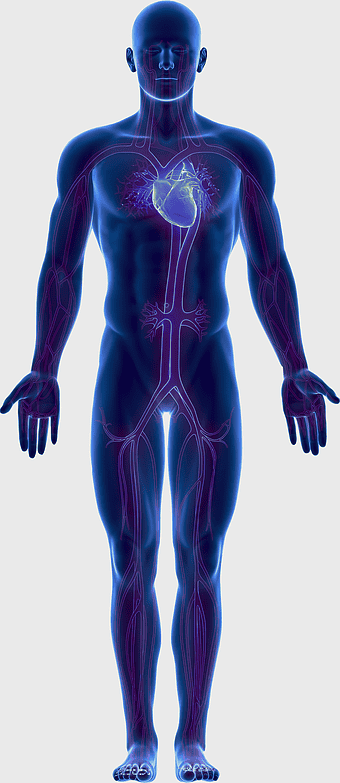

human anatomy illustration, family medicine clinic visuals, blood pressure monitoring, shoulder and hip anatomy, medical diagram of human body, circulatory system depiction, health clinic -

human circulatory system diagram, blood vessel network illustration, human anatomy chart, cardiovascular system overview, human body medical illustration, physiological system depiction, organ function visualization -

human anatomy illustration, purple medical figure, human body healing art, quantum health visualization, anatomical organ depiction, therapeutic body diagram, violet human structure -

blue human anatomy illustration, human circulatory system diagram, digital human skeleton image, electric blue medical figure, human nervous system visualization, human body organ map, human health care graphic -